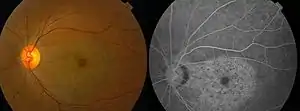

| Chloroquine retinopathy [2] | |

With continued drug exposure, there is progressive development of a bilateral atrophic bull's-eye maculopathy and paracentral scotomata, which may in severe cases ultimately spread over the entire fundus, causing widespread retinal atrophy and visual loss.

Profound abnormalities detected with visual field and multifocal electroretinography testing can be observed in the presence of a normal retinal appearance. Retinal examinations are advised for documentation, but visible bull's-eye maculopathy is a late change,[6] and the goal of screening is to recognize toxicity at an earlier stage. Annual screening should begin after 5 years (or sooner if there are unusual risk factors).[5]